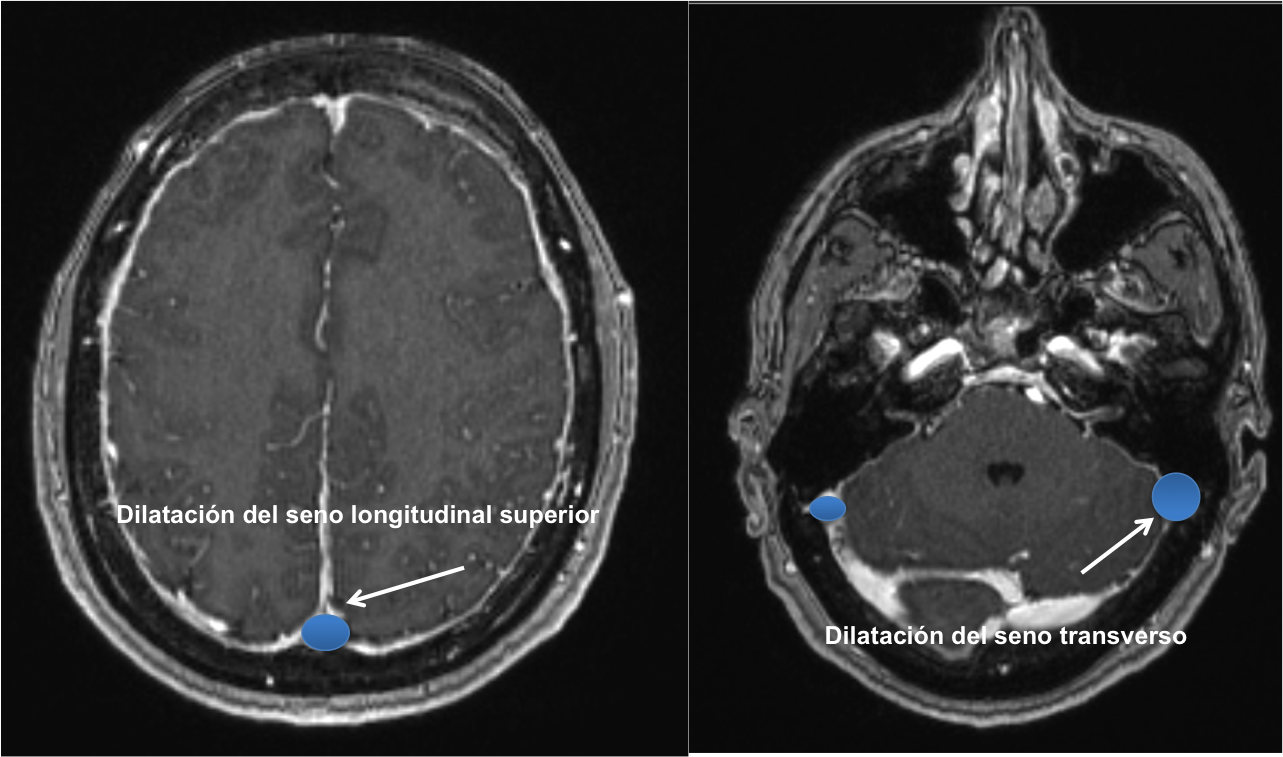

En la Imagen 4 y 5 podemos ver el aspecto congestivo y redondeado de los senos venosos longitudinal y transverso.